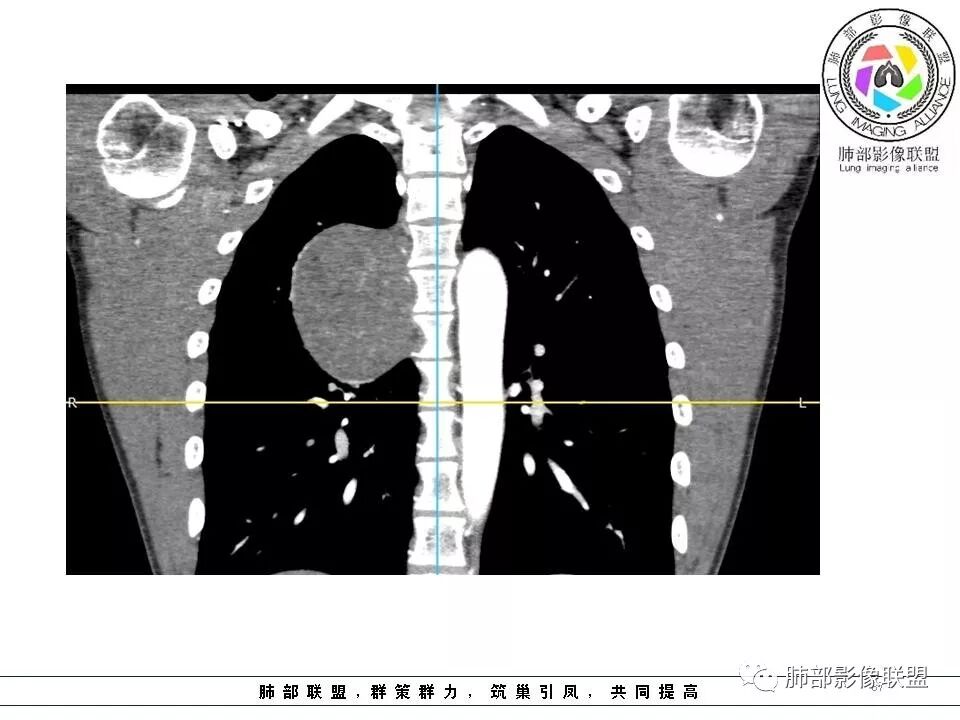

右肺占位,跨越上叶后段、下叶背,边缘光滑,瘤肺界面清,见肺压缩缘(线样不张`强化),见胸膜尾征,胸膜下脂肪未见明显增厚,肋骨丶脊柱未见侵袭及受压,渐进性丶地图样强化,冠状位似见体循环供血

边缘光滑,宽基底与胸壁相连,跨叶裂,叶裂稍前推,血管、支气管前移。

浅分叶

外上侧少量胸水

肋间动脉供血,强化尚均匀,逐步强化

供血,体外供血,体循环,要么是壁层胸膜,要么胸膜外的,脏层胸膜应该是对内供血。病变里面的血管,除非是非常粗大迂曲的血管,不然,我不认为是其特点。

如果一个大的病变,无论胸膜腔内、还是外,它都会将液体局部阻断,因为太大会把局部隆起,胸膜局部推压,哪一方面推压都会阻断。如果幸运看到里面的积液,积液可见渗入到附近间隙,如果在肿块后面肯定是胸膜腔内,在前面,要么是壁层胸膜,要么胸膜外的。

这个胸膜间隙,看起来就是一个脏层胸膜一个壁层胸膜,来源就很多种,胸膜是弧形,不规则半圆,后方的、外侧的、内侧纵隔胸膜、肋胸膜,病变来源很多种,第1肺内的,第2脏层胸膜的,胸壁的、肋间的神经源性。例脏层胸膜的,胸膜本身宽基的,带蒂的朝肺内、带蒂的朝胸膜腔突出的,这些都有差异,壁层胸膜也是。胸膜尾征这个有多大价值,贴近胸膜的病变,压迫、刺激胸膜局限性增厚,我对胸膜尾征价值不踏实,我觉得对胸膜的推移对病变对病变定位反而有价值,好就好在这个区域的病变不多,良性的有推移,恶性的有侵袭性特点,肋骨来源、附近的肉瘤,神经源性肿瘤恶变,间叶组织来源,转移瘤,还有就是全身疾病免疫、血液来源的,我觉得定到胸膜外、如果能定胸膜就定,定不到就定不到,如果是肺内动脉血供,与肺没有关系,定在胸膜,孤立性纤维瘤常见,鞘瘤等罕见。

1.右上胸内脊柱旁类圆形肿块,质地似乎比较坚实,密度稍显不均,但未显示明确的坏死。

2.肋间动脉病供血也提示肿块来自后纵隔?

3.相邻椎间孔未见扩大,也未见块影延入椎管,易起自于神经根的鞘瘤似乎找不到支持点。

可惜未提供矢状位骨窗图像,如在肋骨内下缘观察到压迹有助于肋间神经的鞘瘤的判断,这是因为二者之间密切的毗邻关系。

4.静脉期轻度不均匀强化,注意不是环形强化,亦未见明确的“AB区”,这点也不支持神经鞘瘤。临床及病灶轻度强化都不支持副节瘤。

尽管神经纤维瘤的诊断确实有些出乎意外,但病例开阔了我们的视野。